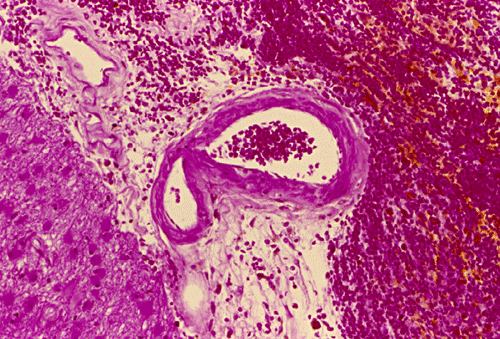

Gross: On external examination of the body, there was no bruising, hemorrhage, or other signs of trauma. The brain weighed 1,300 grams. The cerebellum and brainstem were within normal limits. A large hemorrhage was present in the right frontal lobe (Panel A). The hemorrhage is rimmed by a thin layer of golden brown tissue indicative of hemosiderin deposition that would be produced by old, resolved hemorrhage  (White arrow in Panel A). The hemorrhage also extends into the ventricle, without dilating the ventricles, and into the basal subarachnoid space (Black arrow in Panel A). On the left frontal tip and bilateral temporal tips, there were some small areas of golden brown discolorations in the leptomeninges that were consistent with resolved small subarachnoid hemorrhages.

Histopathology: The hemorrhage, not surprisingly, is composed of blood (Panel B). At the periphery of the hemorrhage are areas that are heavily infiltrated by macrophages accompanied by substantial hemosiderin depositions (Panel C). On medium magnification, the blood vessel walls seems to be thickened and some ill-defined deposition are present in the wall (Arrow in Panel D). Immunohistochemistry for amyloid-b (Ab) was performed and the depositions in the vessel wall are positive.